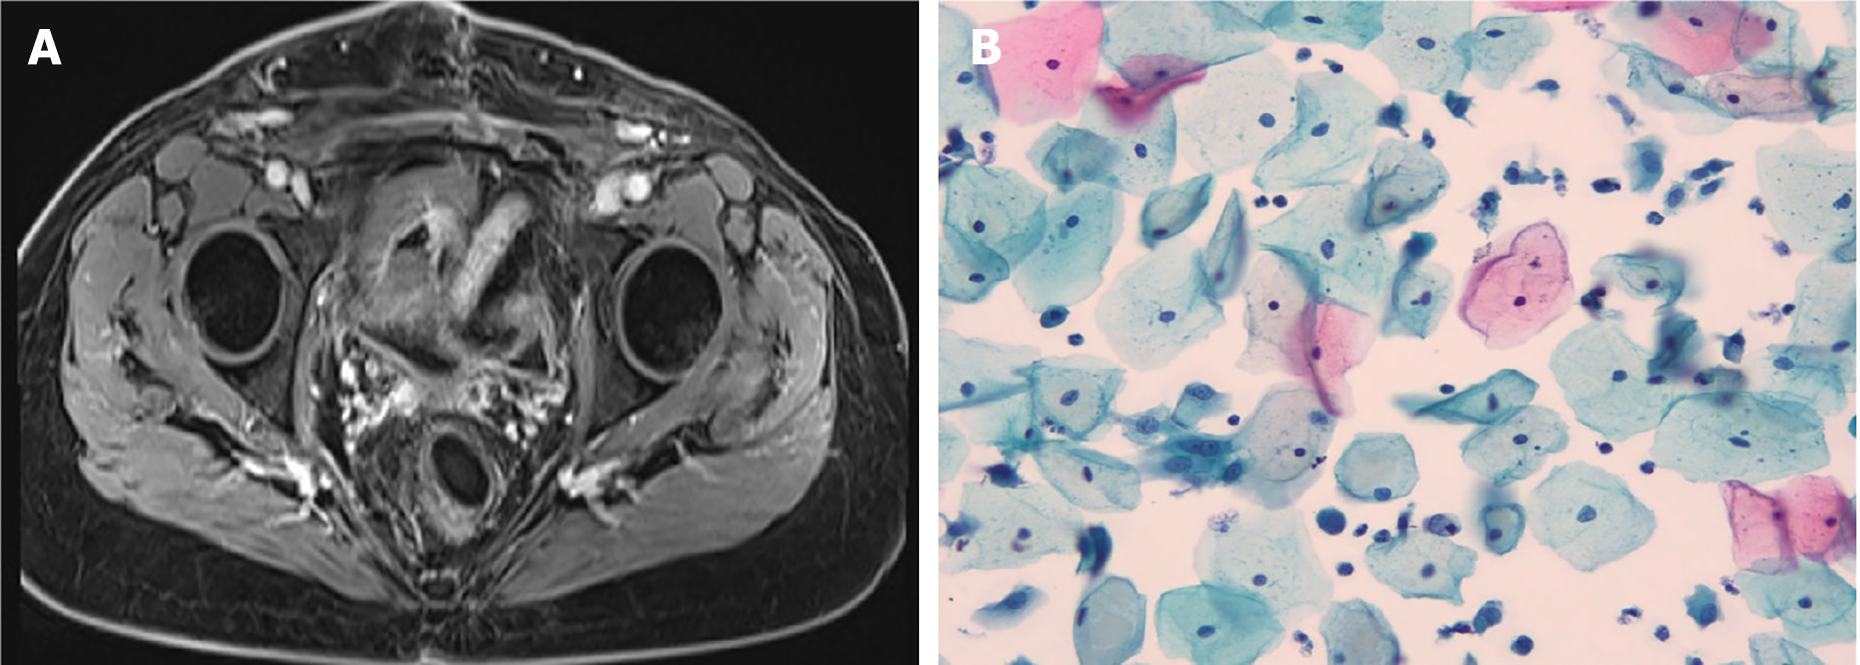

Figure 3 Images of pelvic magnetic resonance imaging and liquid-based cytology.

A: Images of pelvic magnetic resonance imaging with IV contrast scan when followed-up 53 months; B: Images of liquid-based cytology testing of the vaginal during the followed-up 53 months.